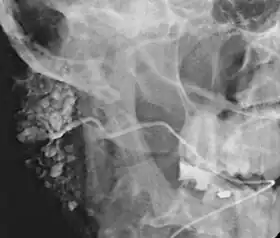

Sialogram in a patient suspected of Sjögren's syndrome

The resulting image is called a sialogram.

This procedure is indicated when there is recurrent swelling and pain on the face but ultrasound has not revealed any problems. If Sjögren syndrome (also known as Sicca syndrome, an autoimmune disease that affects the lacrimal and salivary glands, causing reduced tears and saliva production) is suspected, this procedure is useful. Besides, when interventional proecudre is planned such as stone removal from salivary ducts or dilatation of the strictures in the salivary gland, this procedure is also indicated.[4] However, for those who are pregnant, with allergy to iodinated contrast, and ongoing infection or inflammation of the face, the procedure is contraindicated.[4]

This study is interpreted by evaluating the morphology of the salivary ducts for obstructions and chronic inflammation. Sialodochitis is a term describing dilation of the ducts caused by repeated inflammatory or infective processes. There is also irregular salivary duct stricture (narrowing) of the duct, which creates an appearance known as "sausage link" pattern on a sialogram. Suggestions of abscesses and autoimmune diseases such as Sjögren syndrome can also be elicited. Sialadenitis is inflammation of the salivary glands, which may cause acinar atrophy and create an appearance known as "pruning of the tree" on a sialogram, where there are less branches visible from the duct system. A space occupying lesion that occurs within or adjacent to a salivary gland can displace the normal anatomy of the gland. This may create an appearance known as "ball in hand" on an sialogram, where the ducts are curved around the mass of the lesion.[6]